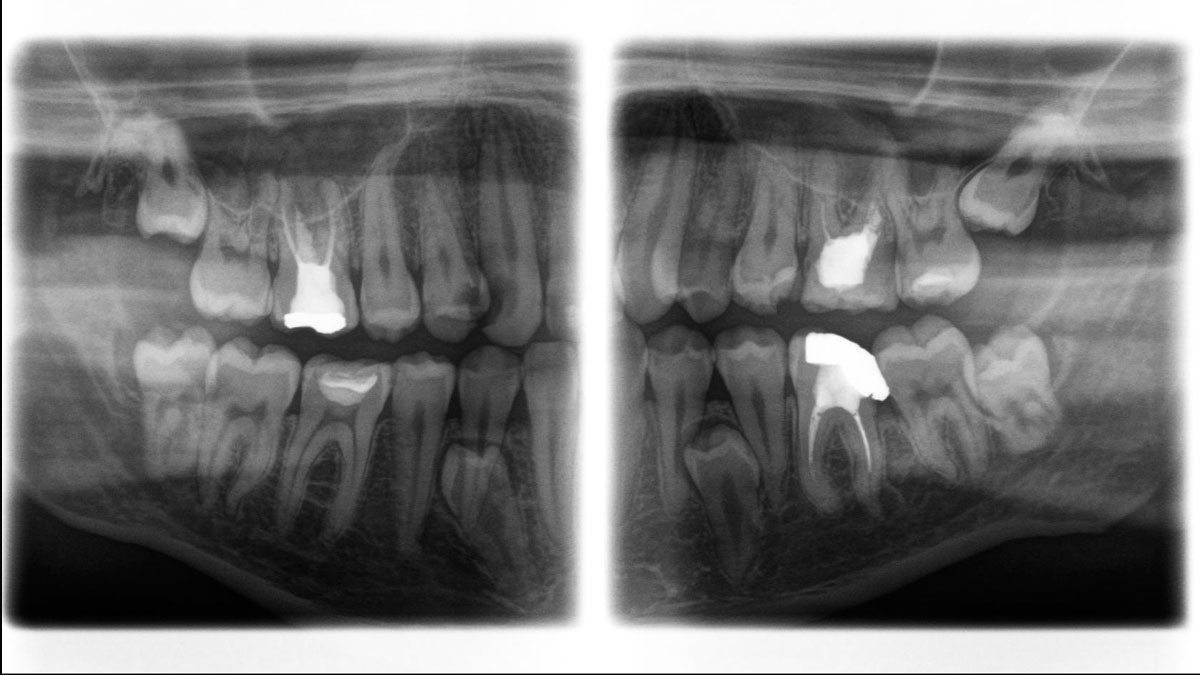

Der Direct Conversion Sensor erfüllt besonders hohe Standards für die 2D-Bildgebung

Der Autofokus erzeugt aus mehreren tausend Einzelbildern automatisch eine beeindruckende scharfe Panorama-Röntgenaufnahme

Der Direct Conversion Sensor (DCS) hat den Standard der Panorama-Bildgebung neu definiert. Röntgenstrahlen werden direkt in elektrische Signale umgewandelt – im Gegensatz zu herkömmlichen Systemen gibt es keinen Signalverlust durch Lichtumwandlung, was eine verbesserte Bildgebung ermöglicht. Das Ergebnis sind Bilder mit einer sehr hohen Schärfe, selbst bei niedriger Dosis.

Eine Röntgenaufnahme muss sofort diagnostizierbar sein. Der Autofokus hilft dabei erheblich. Orthophos SL erfasst mehrere tausend Einzelbilder in einem Zyklus und erkennt automatisch scharfe Bereiche, um ein gleichmäßig scharfes Gesamtbild zu erzeugen. Der intelligente Autofokus erfordert keine manuellen Arbeitsschritte vor und nach der Erfassung.